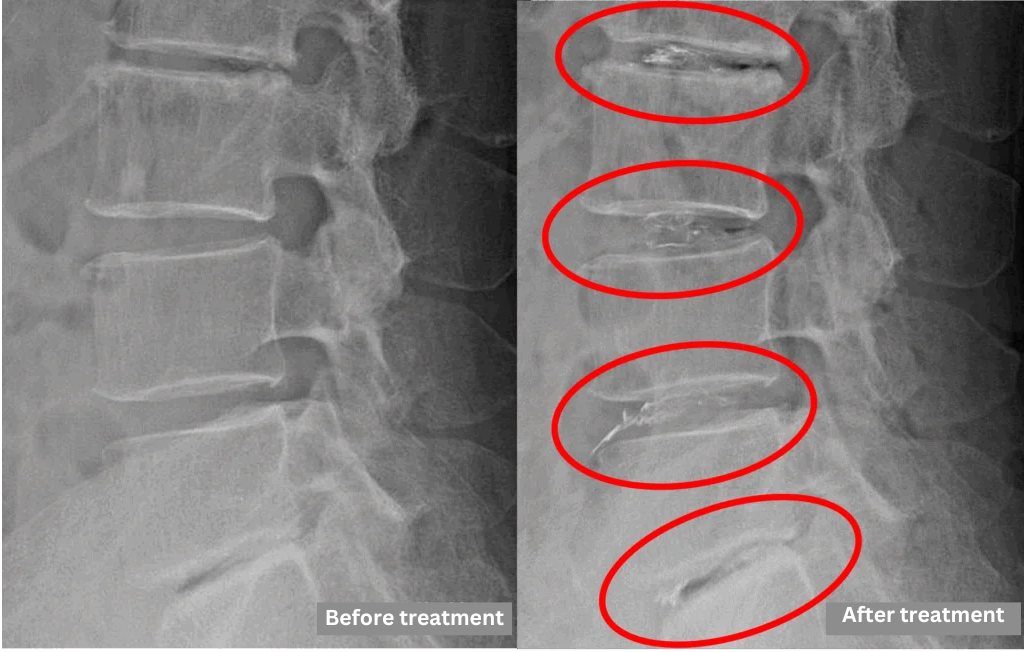

- L2/3, L4/5, L5/S – Disc degeneration, bulging

- L3/4 – Disc degeneration, bulging, spinal canal stenosis

The above findings were also observed on the imaging.

Based on imaging, compression of the spinal canal from disc changes at L2/3, L3/4, L4/5, and L5/S is considered the likely cause of symptoms.

The Cellgel Method was performed on four levels (L2/3, L3/4, L4/5, and L5/S), following consultation with the patient.